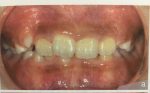

先程の写真の10歳のお子さんは、

歯の矯正も含め、黒ずんだ歯ぐきの除去、

歯ぐきの形態を変える手術も行い、

このようにキレイになった

そうです。

(先程の写真の10歳のお子さんが、

23歳になったときの写真です)